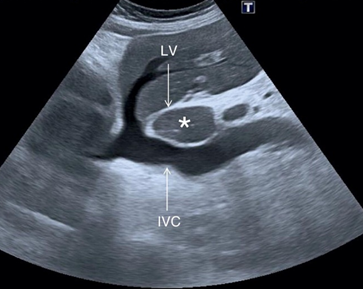

The caudate lobe is a small, anatomically distinct lobe of the liver located on the posterior surface, nestled between the inferior vena cava (IVC) and the ligamentum venosum. Despite its small size, it has separate vascular supply and venous drainage, making it functionally significant.

Key Sonographic Points:

1. Posterior to the porta hepatis

2. Bounded by the IVC (right side) and ligamentum venosum (left side)

3. Lies superior to the caudate process, above the porta hepatis

• Right: IVC

• Left: Ligamentum venosum

• Inferior: Porta hepatis

• Anterior: Posterior segment of the left lobe

• Ultrasound Appearance:

• Seen posterior to the liver hilum in a transverse epigastric scan

• May appear prominent in cases of liver cirrhosis (caudate hypertrophy)

• Key landmark in evaluating portal hypertension